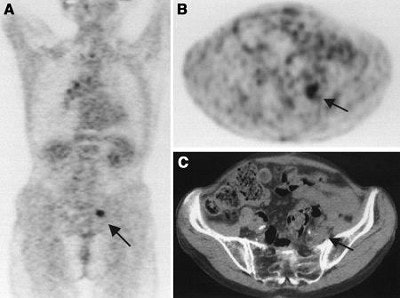

| A 75-year-old woman after resection of rectal carcinoma. Before FDG-PET imaging, curative radiotherapy was planned. Coronal (A) and transverse (B) scans show previously unknown iliac internal lymph node metastasis (arrow). Correlating CT scan (C) does not show any metastases. Treatment was changed from curative to palliative treatment (chemotherapy). Image and caption courtesy of Dr. Elena Dizendorf and the Journal of Nuclear of Medicine. |